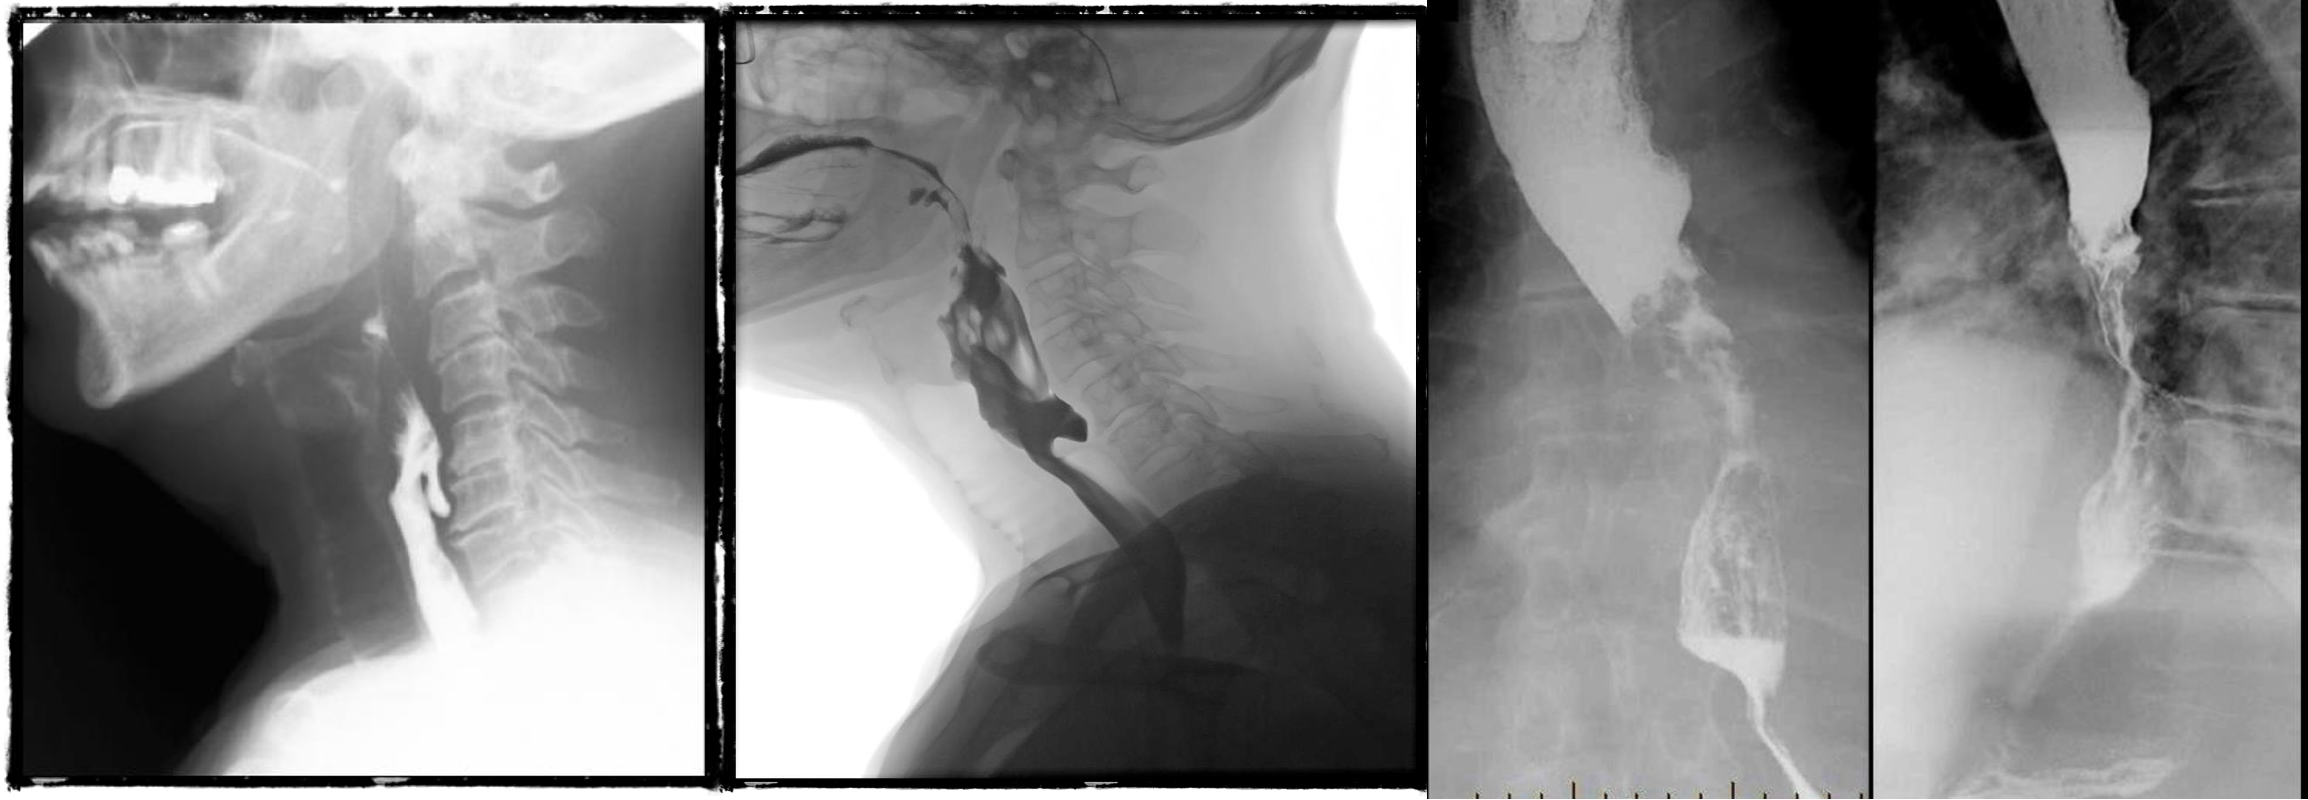

- barium swallow - zenkers diverticulum

- negative

- b swallow - diltation upper, stricture (diff cancer)

- normal (mucosal fold roge)

- dilated esophagus, stricture, bear beak/rat tail sign = aclasia

Pharyngeal pouch, zenkers diverticulum

1,2,3- valsava maneuvear - laryngocele